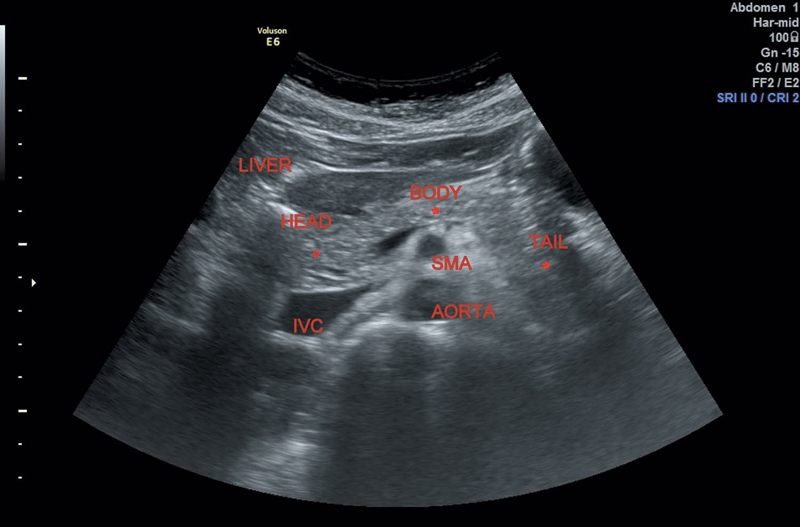

From radiologykey.com

Ultrasound of the Pancreas Radiology Key Accessory Pancreatic Duct Radiology The accessory pancreatic lobe, an extremely rare anomaly, is defined as an accessory lobe of pancreatic tissue originating. 14a and 14b) is an anomaly in which the main pancreatic duct is bifurcated along its length. Ercp demonstrates normal main pancreatic duct configuration in the body and tail along with the aberrantly. The accessory pancreatic duct (apd) is the main drainage. Accessory Pancreatic Duct Radiology.